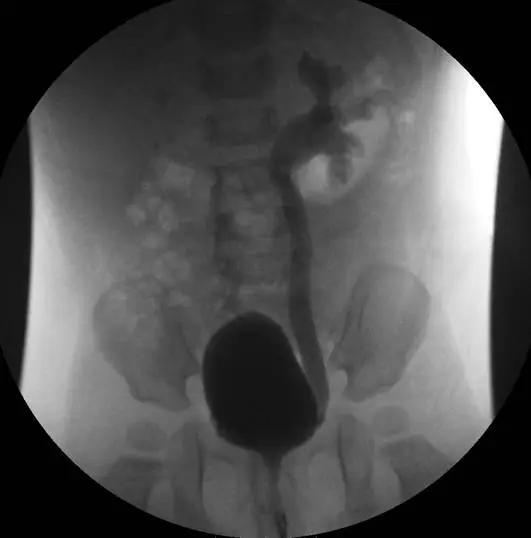

一個 8個月大的男童因第一次尿道感染住院,膀胱尿道攝影檢查( voiding cystourethrogram )顯示如附圖,你會如何給父母親建議?

VCUG 圖像顯示:

- 膀胱:中央可見充滿顯影劑的膀胱(黑色卵圓形陰影)

- 雙側輸尿管逆流:可見顯影劑由膀胱逆行進入雙側輸尿管,左側更為明顯,輸尿管有明顯擴張

- 腎盂積水:左側腎盂可見顯影劑充填,且有輸尿管迂曲擴張之表現

- 分級判讀:雙側輸尿管有擴張(ureter dilation)且腎盂有充填,左側約達 Grade III–IV(輸尿管、腎盂、腎盞擴張,腎盞穹隆部輕至中度變形)

此影像表現為雙側中至高度 VUR,對 8 個月大嬰兒而言,依指引應給予抗生素預防感染。